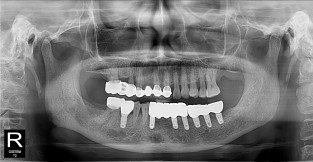

하악

치료기간 : 2021-11-30 ~ 2022-07-13

1. 상기 x-ray 이미지 모두 동일한 해당 의료기관에서 진료한 환자입니다.

2. 상기 x-ray 이미지 모두 동일 인물의 것입니다.

3. 치료 전 이미지는 2021-11-30에 촬영했으며, 치료 후 이미지는 2022-07-13에 촬영하였습니다.

4. 상기 x-ray 이미지 모두 동일 조건에서 환자분의 동의를 받아촬영되었습니다.

* 임플란트 시술은 환자분의 상태(고혈압, 당뇨 등)에 따라 부작용이 있을 수 있으니, 반드시 전문의와 상담이 필요합니다.

* 임플란트 수술 부작용

: 수술 후 출혈, 교합, 통증, 붓기, 염증 등의 문제점이 발생할 수 있습니다.)

* 본 이미지들은 의료광고법을 준수하여 게시하였으며, <의료법 제 56조 제2항 제7호>에 의거하여 개개인의 신체 상태와 질병 진행도 등 여러 요인에 따라 치료 효과가 상이하기에 진료계획 또한 달라질 수 있음을 고지해드립니다.